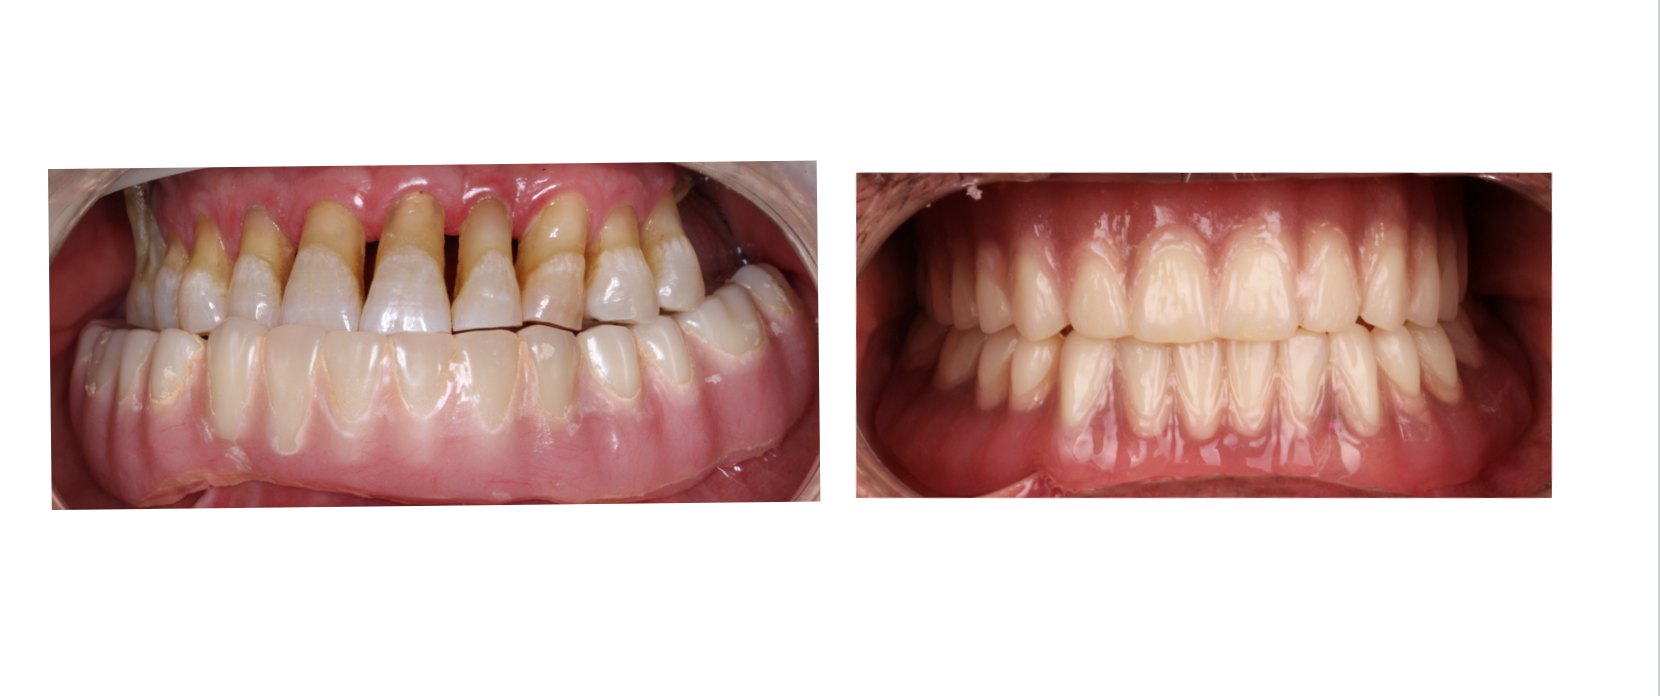

“La prótesis adecuada transforma mucho más que una sonrisa: mejora tu vida.”

Soy Gabriela González, especialista en prostodoncia comprometida con restaurar la función, estética y confianza de cada paciente.

Mi objetivo es ofrecer tratamientos personalizados que se adapten a tus necesidades, combinando técnicas tradicionales con tecnología moderna para lograr resultados naturales, cómodos y eficientes.

Cada caso representa una nueva oportunidad de ayudarte a volver a comer, hablar y sonreír sin limitaciones, con la seguridad y bienestar que mereces.

Prótesis fija

Coronas, puentes y rehabilitaciones completas.

Diseño de sonrisa

Armonización estética con enfoque funcional.